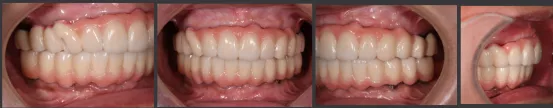

即刻修复后患者的正侧貌美学评估:

正貌美学评估:

· 面部对称、三等分,面中线与中切牙中线一致,上下唇可自然闭合。

· 侧貌美学评估:

· 上唇丰满度:适中,鼻唇角105°,上下唇位于美学E线,直面型。

· 预告面型及修复后与修复前对比,患者的正侧貌美学得到了极大的改善,凸面型变为直面型。

· 第二幅临时修复体戴入口内,修复效果良好,前伸侧方咬合无干扰,预留清洁通道。

· 修复体红白美学满意,前伸侧方咬合均无干扰,前牙前突问题解决,指导患者清洁。